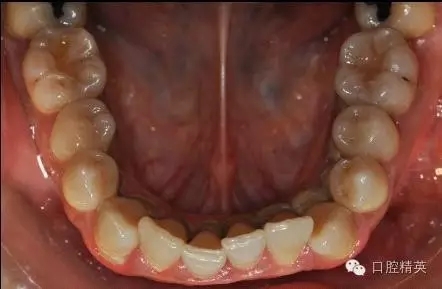

本病例 :女 34歲,主訴刷牙出血,覺(jué)牙齒輕度松動(dòng)一年。

檢查見(jiàn)大量齦上及齦下結(jié)石,探診出血,牙周袋較深,32-42 II度松動(dòng)。X線片顯示牙槽骨水平吸收。

診斷:成人慢性廣泛性中度牙周炎。

治療前: